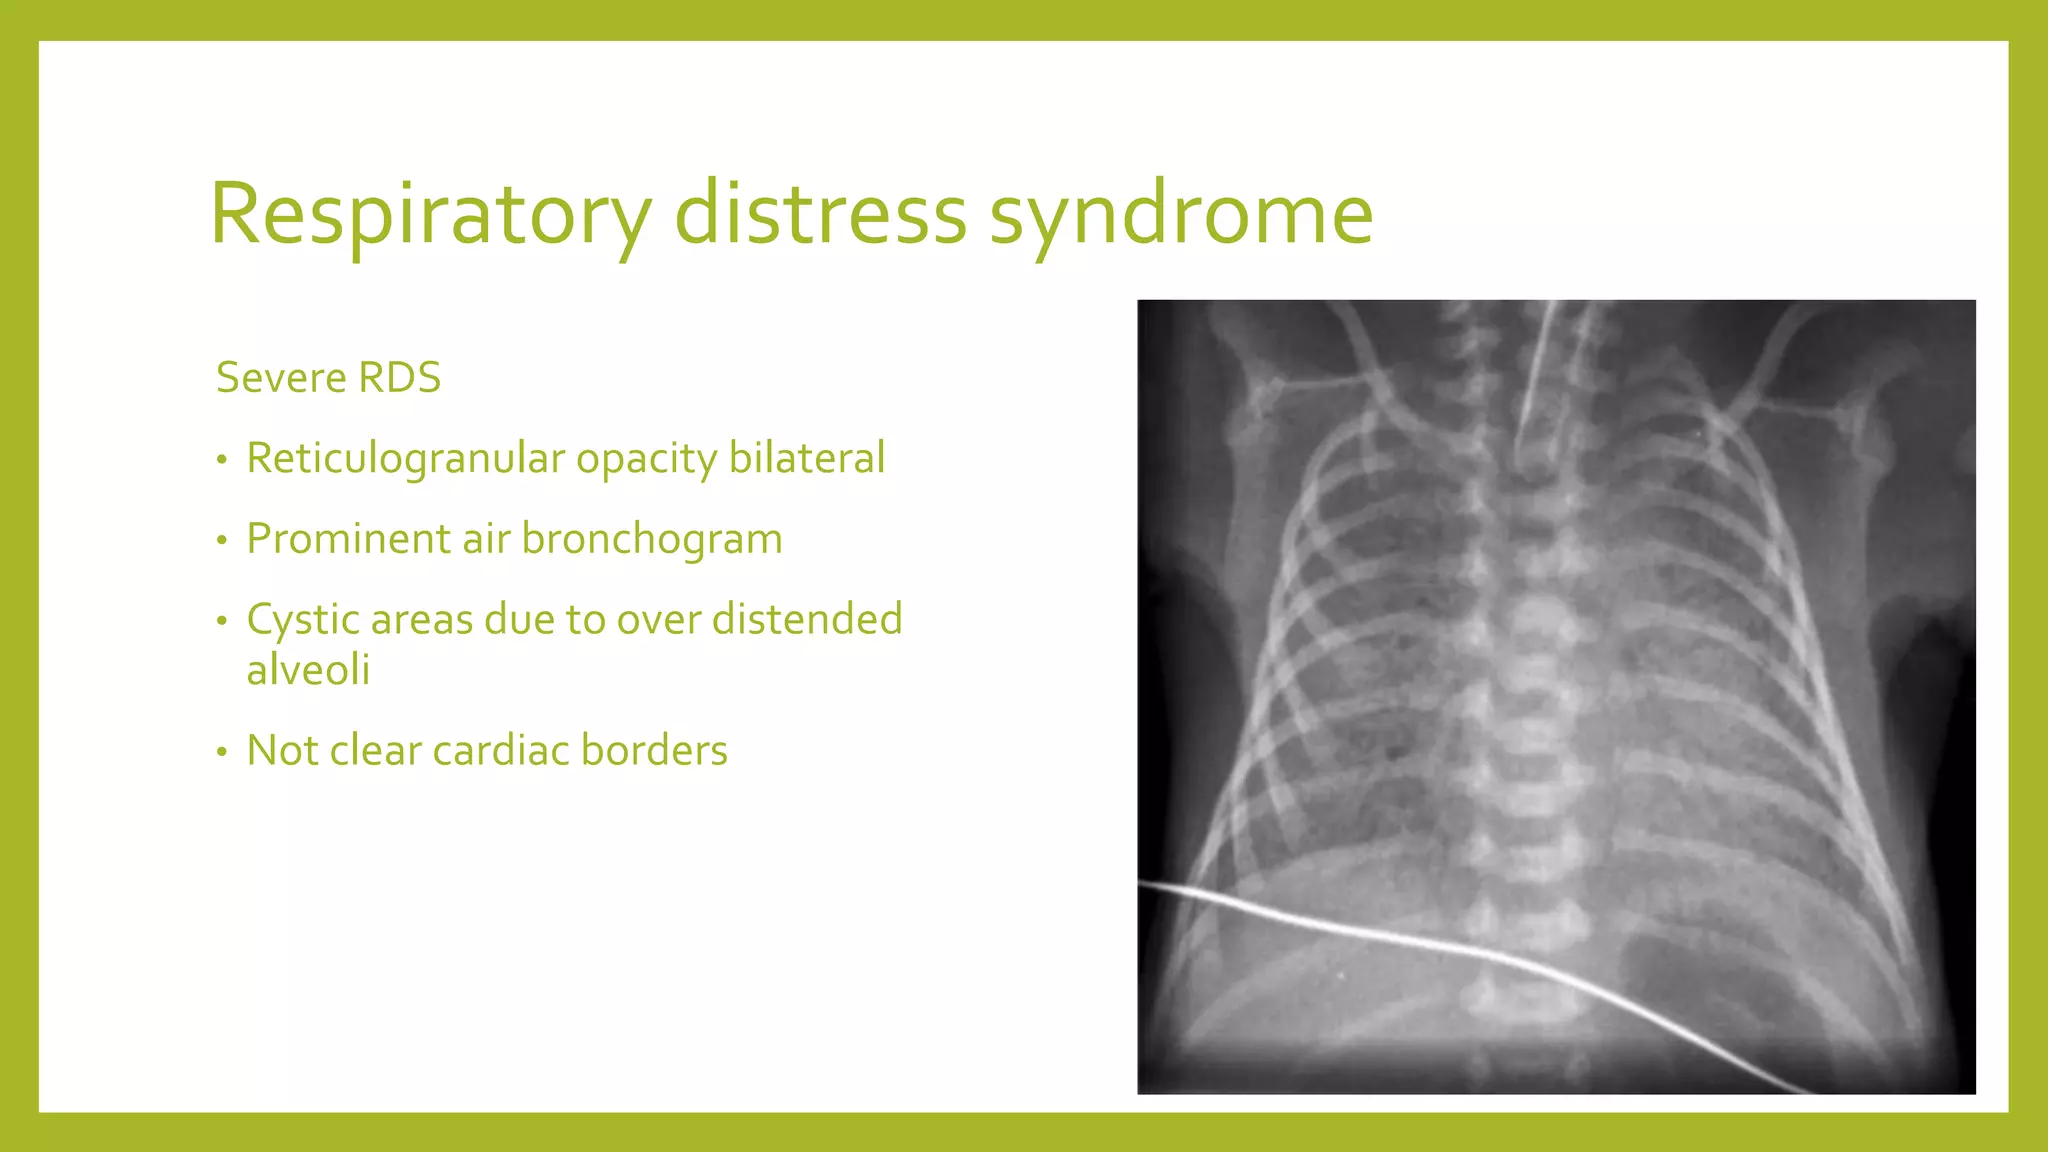

The document provides guidance on approaching and interpreting chest x-rays (CXR). It outlines steps to check the name, date and quality of the film, systematically scan the CXR looking for abnormalities, and determine if the lungs appear too white or black. Specific signs are described to help localize abnormalities, including the cardiac silhouette sign and pleural effusion signs. Examples are given of respiratory distress syndrome, tetralogy of fallot, transposition of great arteries, and total anomalous pulmonary venous return. The take home message is to summarize positive findings, compare to prior CXRs if available, and confirm findings with a radiologist.